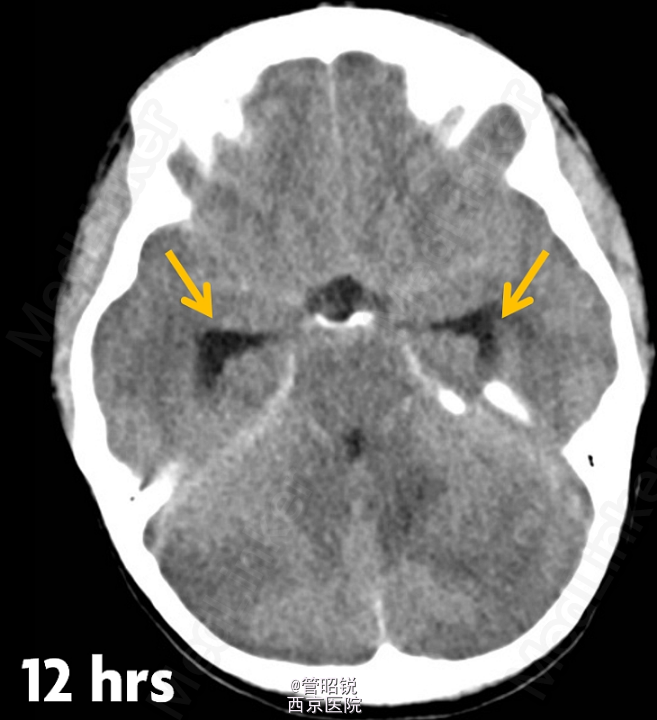

患者,男,29岁,头痛、颈痛2周 入院时CT正常,24小时后 T2WI (B) 和 T2W-FLAIR (C)显示高信号增强,脑水肿,沟回消失。CE-T1WI (D)显示脑膜线样增强。随后12小时的非增强CT显示小脑水肿压迫脑干,由于阻塞性脑积水使颞角膨大,需要紧急行颅后窝颅骨切除减压术。(影像资料比较典型。和大家分享下 AJNR-case of the week)

诊断:急性小脑炎 治疗上应早期应用激素治疗,水肿严重时应手术行颅骨减压。